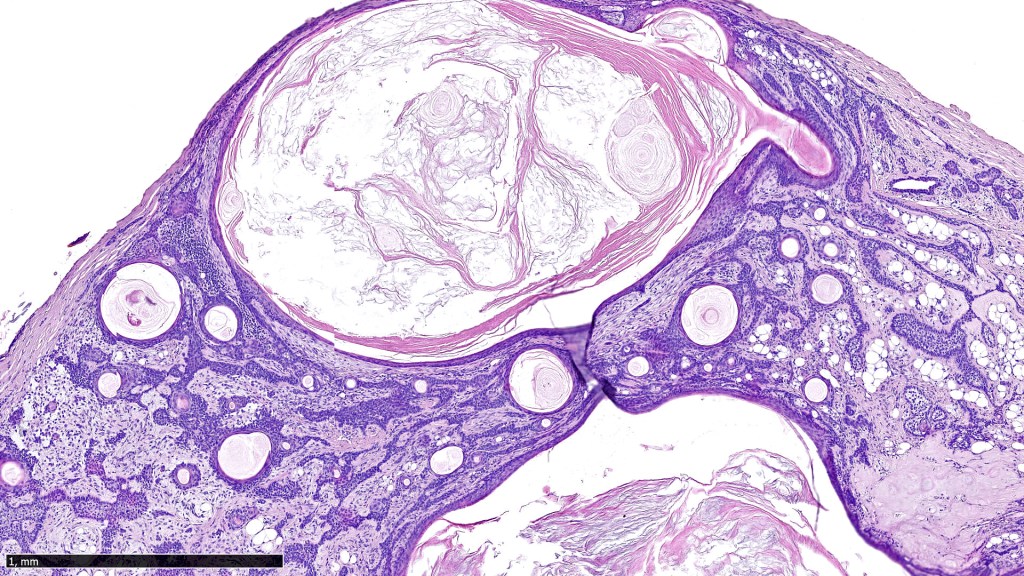

•Well circumscribed unencapsulated, nodular/multinodular silhouette composed of an admixture of epithelial & mesenchymal elements

•Follicular & sebaceous differentiation

•Keratocysts & squamous foci

•Stromal sclerosis & hyalinization

•Myxoid change

•Chondroid foci